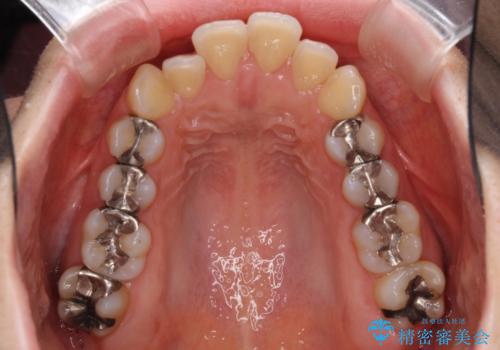

- 上下の出っ歯を気にして来院された患者様です。

口元を積極的に引っ込めるために、上下左右の第一小臼歯を4本抜歯することとしました。

元々ディープバイトのため、スペースを閉じている期間に上下前歯が接触してしまい、治療期間が想定よりも伸びてしまいました。